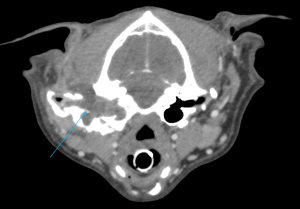

CTでは左耳の耳道、鼓室胞の中に充実性の病変が見られ、耳道の骨は一部融解していました。CTの所見から真珠腫性中耳炎が疑われました。真珠腫は外耳炎などにより鼓膜が破れ、鼓膜の内側の中耳内、鼓室胞に上皮細胞が浸潤することで慢性的に炎症が起こり、痛みや神経症状、開口障害といった症状が出ます。

今回は神経症状はありませんでしたが、痛みや開口障害は出ていましたため、さらに進行していく前に外科手術で治療しました。手術は全耳道切除術、鼓室胞切開を行い、外側から耳道を切除し、鼓室胞の中をしっかり剥離、洗浄しました。切除した組織を病理検査に提出し、返ってきた結果は慢性外耳炎と鼓室胞の真珠腫でした。